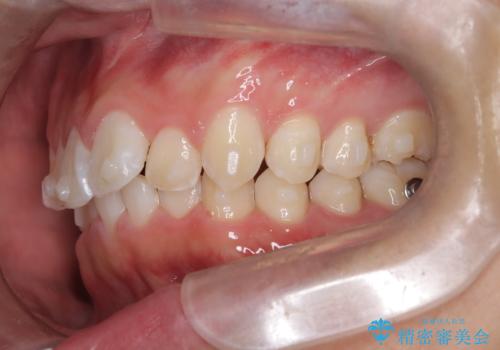

- 歯のデコボコと過蓋咬合を主訴に来院された患者様です。

アーチの拡大とIPRを行い非抜歯で治療を行いました。

歯を抜かずに叢生(デコボコ歯列)と過蓋咬合を改善する事が出来ました。

インビザラインによる治療でも十分に美しい歯並びを実現でき、患者様にも大変ご満足いただけました。